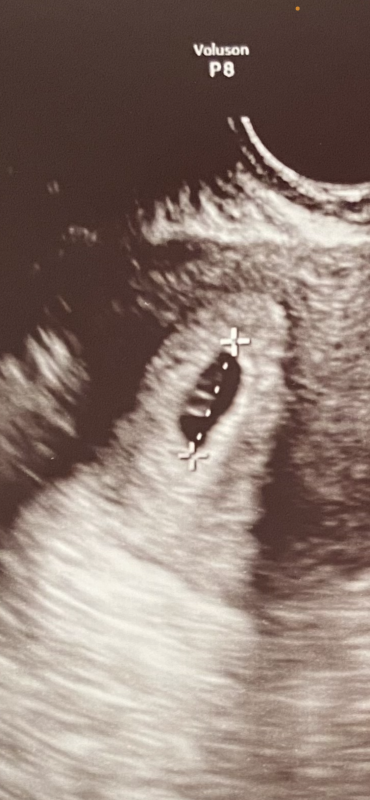

不妊治療を経て初めて陽性反応が出ました。本日で5w2dで経過観察してきました。無事に胎嚢確認ができ、大きさは12mmでした。

家に帰ってエコー写真をよくよく胎嚢をみると卵黄嚢らしき物が2つあることに気がついたのですがこれは双子の可能性はありますか?

お写真からですと、はっきりとはわかりませんが、お写真の少し薄めの丸いものが、おっしゃるように卵黄嚢ではないかと思います。医師から双胎妊娠などの指摘がなかったということでしたら、少し濃い色をしている部分は、おそらく赤ちゃんの部分ではないかと思いますが、お写真からですとはっきりとは判断しにくいので、あまりお役に立てなくて申し訳ありませんが、次回の健診時に再度ご確認いただけたらと思います。よろしくお願いします。